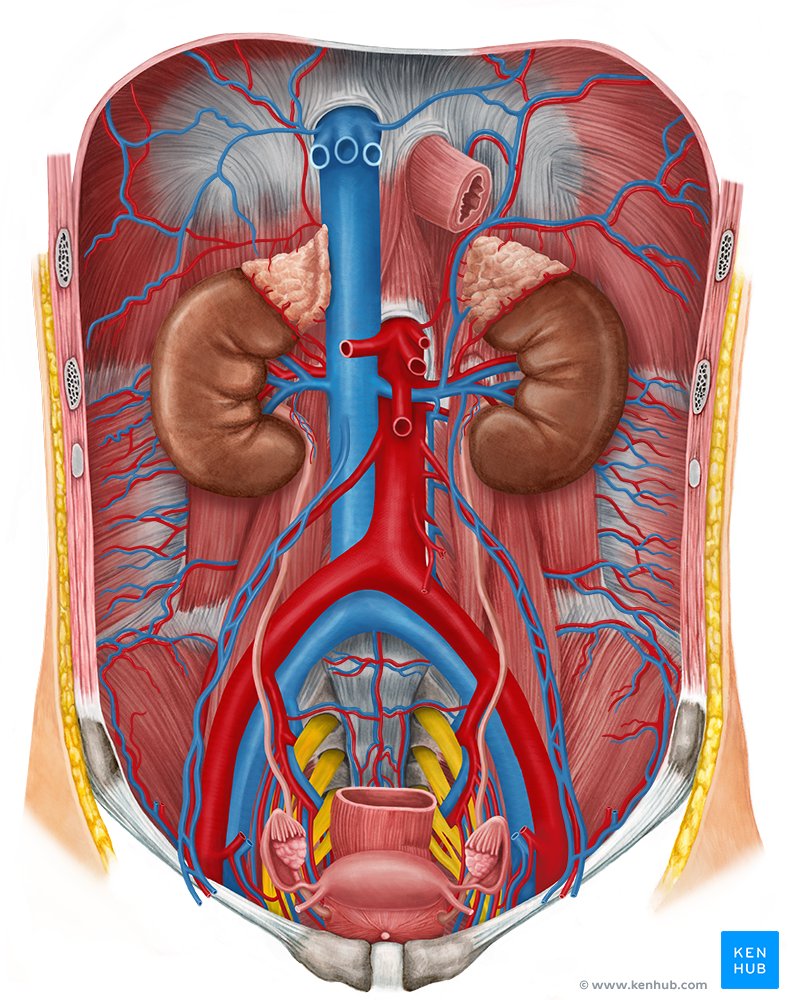

Cómo funcionan los riñones y su relación con las pastillas

Los riñones son los filtros de nuestro cuerpo. Cada día, procesan aproximadamente 180 litros de sangre, eliminando desechos y regulando el equilibrio de agua, sales y minerales. Algunas pastillas, como las destinadas a la presión arterial, afectan cómo circula la sangre por estos órganos, pero eso no significa automáticamente que los dañen.

Sorpresa: la investigación muestra que ciertos medicamentos antihipertensivos en realidad protegen la función renal cuando se usan correctamente.